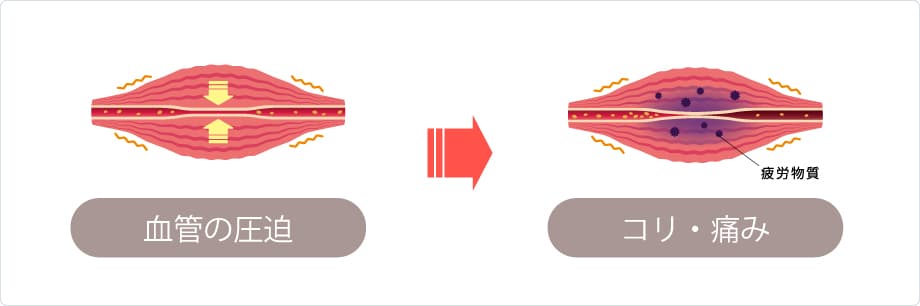

筋肉は血液から酸素やエネルギーをもらい正常に動きます。しかし、同じ姿勢や同じ動作を続ける事で筋肉に負担がかかり血流不足となりしびれが引き起こされます。

しかし、しびれがある筋肉は、血流不足により必要なエネルギーが筋肉に運ばれず筋肉がSOSを出している状態です。

この状態が続き負担がかかり続けると、筋肉は次第に硬くなり、皆さんが感じられる【コリ】となります。この筋肉のコリ・しこりのことを医学用語で【トリガーポイント】といいます。